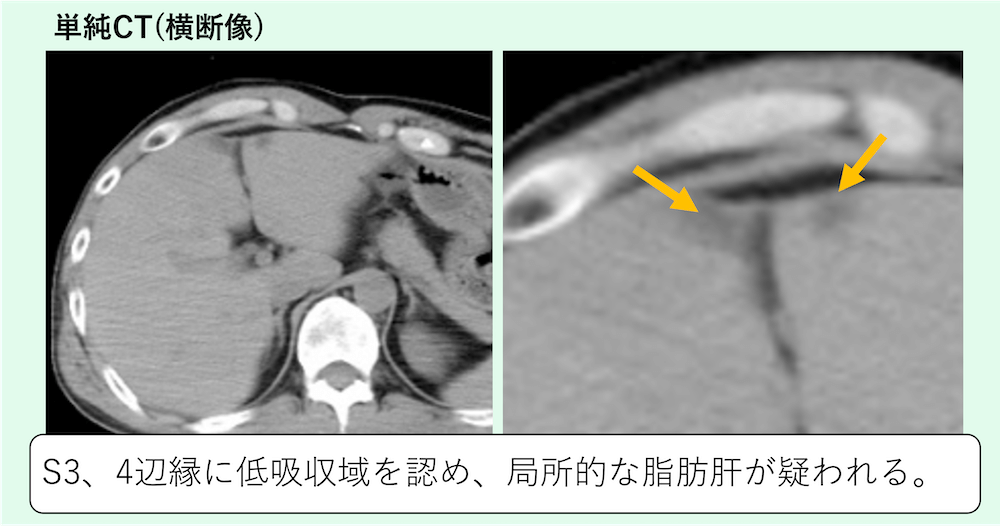

症例 70歳代男性

S3、4辺縁に低吸収域を認め、限局性脂肪肝(focal fatty liver)が疑われます。